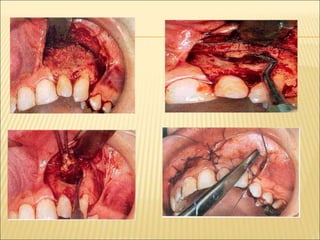

 Enucleation with primary closure-

Anaesthesia

Incision- envelope flap

trapezoidal

Elevation of Mucoperiosteal flap

Bone removal

Exposure of cystic lining

Try to remove entire cyst lining in a single

piece

Irrigation of cavity and hemostasis ensured

suturing